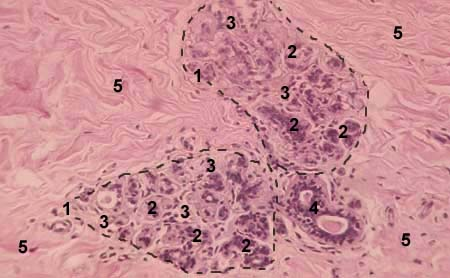

Рисунок 3- Нелактирующая молочная железа 1-дольки железы; 2- зачатки концевых секреторных отделов; 3-внутридольковая соединительная ткань; 4- междольковый выводной проток; 5- междольковая соединительная ткань Кровоснабжение молочной железы осуществляется в основном внутренней грудной (a.mammaria interna, ветвь a.subclavia) и боковой грудной(a.thoracica lateralis, ветвь a.axillaris) артериями. Задняя поверхность железы снабжается кровью от проникающих в неё тонких ветвей межрёберных артерий (rami a.intercostales, от третьей до седьмой). Все артерии анастомозируют между собой и окружают железистые дольки и протоки артериальной сетью. Глубокие вены сопровождают артерии и вливаются в подмышечную и надключичную вены, во внутреннюю грудную и верхнюю полую вену. Поверхностные вены образуют подкожную сеть, связанную с подмышечной веной.